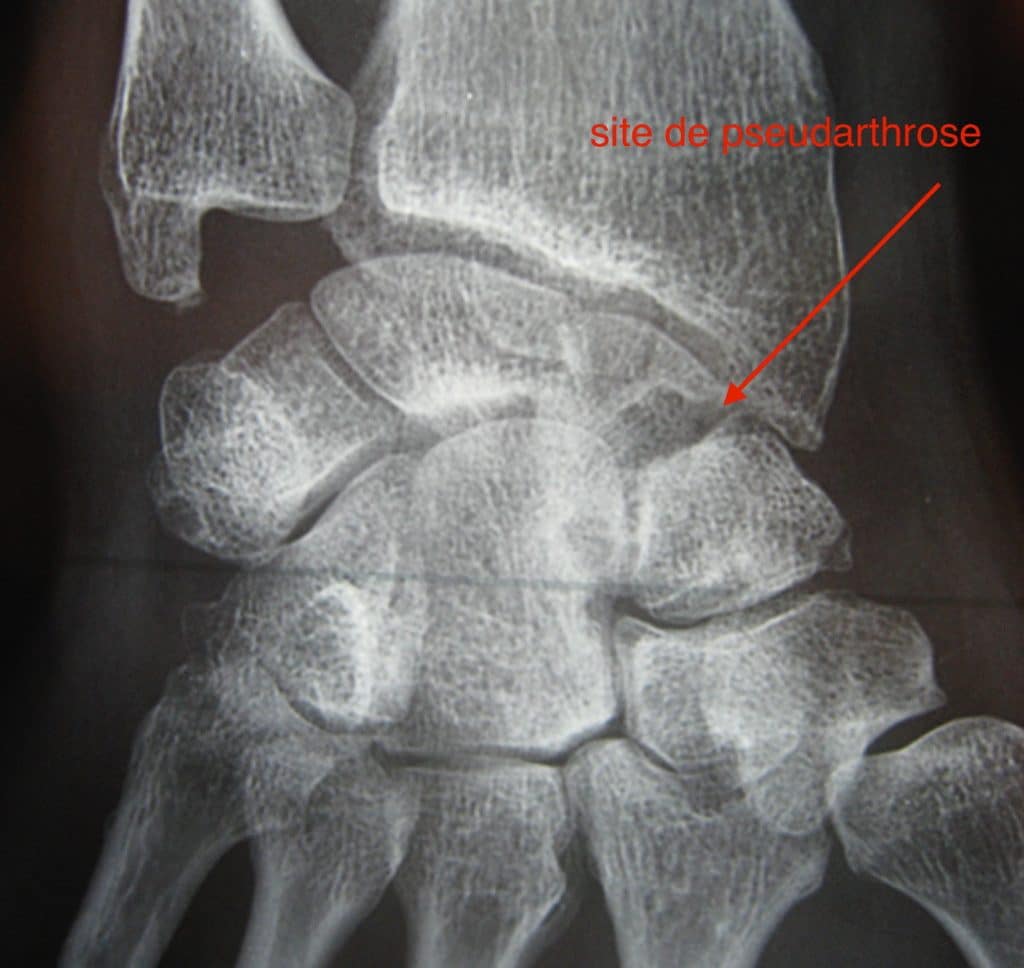

Pseudarthrose du scaphoïde

Suite à une fracture du poignet, du fait de sa vascularisation particulière, si la fusion des pièces osseuses ne se fait pas, on parle de pseudarthrose du scaphoïde. Il s’agit d’une absence de consolidation des deux morceaux du scaphoïde Au-delà des délais habituels (6 mois), douleur et parfois gonflement du poignet invitent à un bilan radiographique, afin d’établir le diagnostic. Lorsqu’il est confirmé, un scanner et une IRM sont nécessaires afin d’établir le stade selon de l’affection et l’état de vascularisation de la partie haute du scaphoïde.